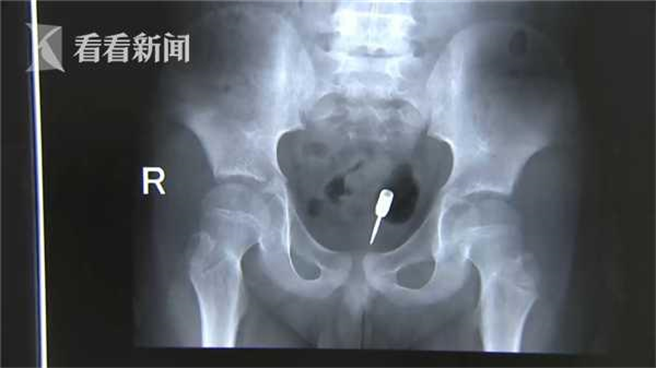

兒童拿來當玩具的物品一定要特別注意,以免孩子發生意外!暑假到來,大陸一名9歲幼童因為沒有安排暑期課程而在家玩耍,但他竟趁家人不注意時,將一支飛鏢塞進肛門;醫生照了X光片,發現飛鏢尖端位置相當危險,但男童的腸道卻沒有受傷,原來飛鏢竟直接刺在糞便上,真是不幸中的大幸!

據《看看新聞》報導,這件意外發生江蘇省海安市,收治男童的消化內科醫生表示,一聽到男童將飛鏢塞進肛門就覺得情況相當緊急,「這種情況如果時間長了,或者小孩運動了以後,這個飛鏢一端是尖的,而且尖端朝向下方的,正好朝向運動的方向,這種情況就容易引起小腸穿孔出血或者感染。」

男童入院後立即接受大腸鏡檢查,醫生發現大腸有一塊較大的糞便,繼續深入40公分發現腸道都很乾淨,於是懷疑飛鏢可能在剛剛腸鏡看到的糞便裡面。醫生說:「我們把糞塊往上推,防止飛鏢的尖端刺到直腸粘膜,推上去我們探查以後確認,這個飛鏢沒有刺到腸壁。」

醫生在男童大腸內注入大量生理鹽水,不但可以保護腸黏膜,還能促進男童排便,最後終於在一大塊糞便中找到尖銳危險的飛鏢,讓男童父母終於安下心來。醫生說:「遇到這種情況,盡量不能等,還是要盡快到醫院,第二個不能通過簡單的灌腸來處理這個事情,還是要在腸鏡下觀察,保證安全的情況下取出患者異物。」